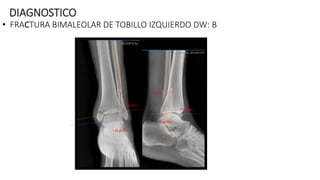

DIAGNOSTICO

• FRACTURA BIMALEOLAR DE TOBILLO IZQUIERDO DW: B

PLAN QUIRUGICO 07-06-24:

-OSTEOSINTESIS CON PLACA TERCIO DE TUBO DE 3.5 MM DE 10

ORIFICIOS+ OSTEOSINTESIS CON TORNILLOS MALEOLARES DE 45 MM

CONTROL DE RX POST QUIRURGICOS